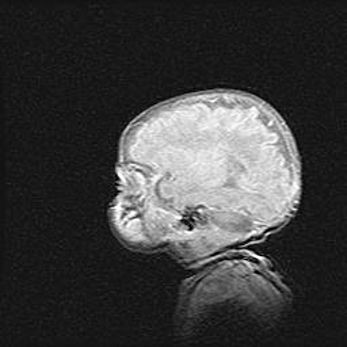

Лейкомаляция с кистозно-глиозной дегенерацией головного мозга.

Возраст: 2 месяца 25 дней

Вес: 6400 г

Окружность головы: 40 см

Срок гестации: 41 неделя

Лейкомаляцию относят к ишемически-гипоксическим повреждениям головного мозга, диагностируемым у новорожденных. При лейкомаляции в головном мозге обнаруживают очаги некроза, возникшие после тяжелой гипоксии и нарушения кровотока. В процессе морфогенеза очаги проходят три стадии: 1) развития некроза, 2) резорбции и 3) формирования глиозного рубца или кисты. Перивентрикулярная лейкомаляция (ПЛ) встречается примерно в 12% случаев среди новорожденных, обычно – у недоношенных детей, причем, частота ее зависит от массы, с которой младенец появился на свет. Наибольшее число малышей страдает лейкомаляцией, если масса при рождении 1500-2500 г.